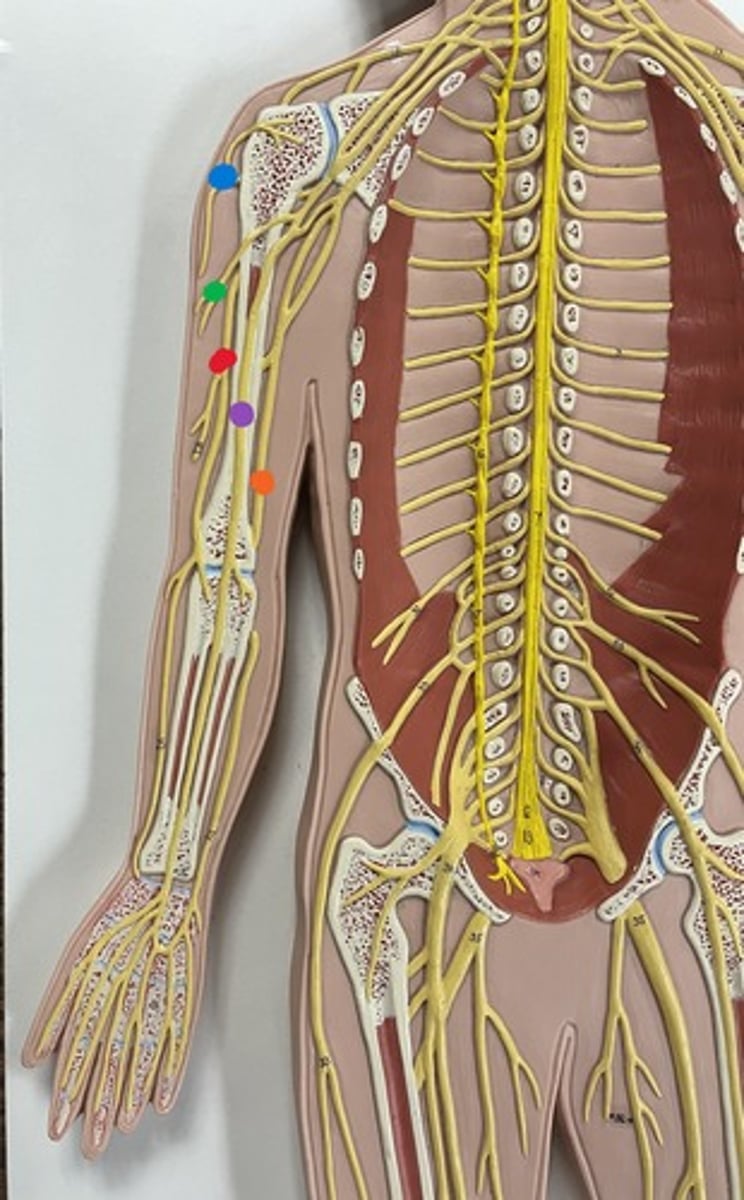

Brachial plexus

Axillary nerve

blue

Musculocutaneous nerve

green

Median nerve

purple

Ulnar nerve

orange

Radial nerve

red